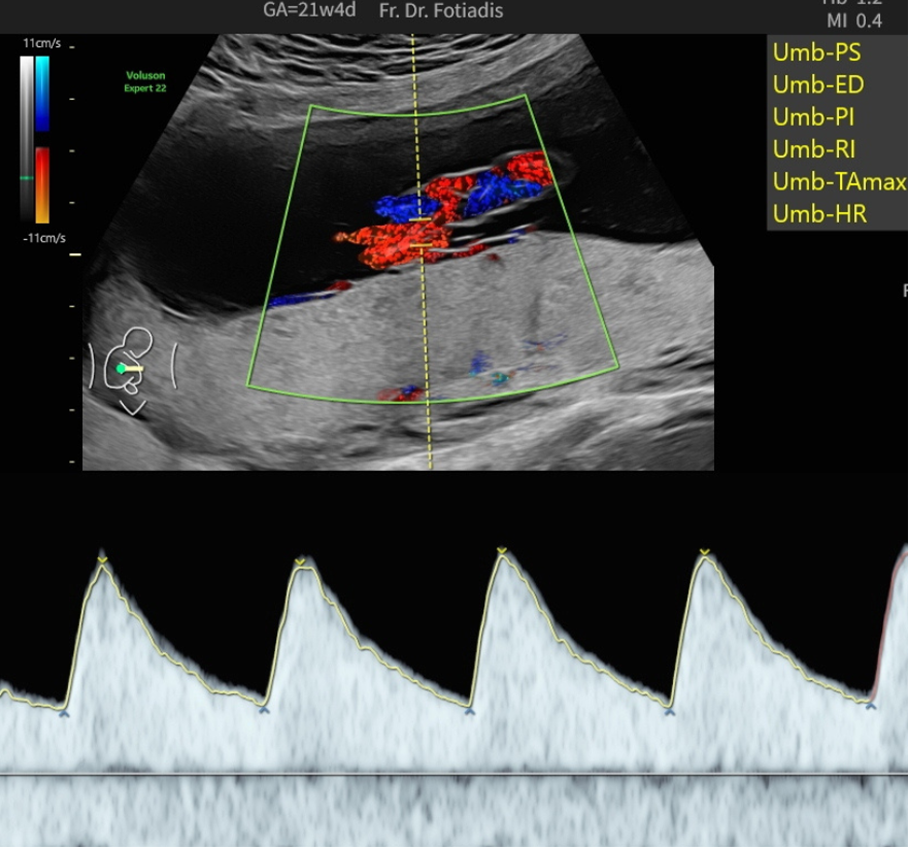

Diese spezielle Untersuchungsmethode dient der Überprüfung von Blutflüssen und Flussgeschwindigkeiten in der Gebärmutter und in verschiedenen kindlichen Blutgefäßen. Mittels Dopplersonographie sind wir in der Lage, die Blutversorgung wie auch die Herzfunktion und Kreislaufsituation des Kindes zu beurteilen. Ebenso kann eine fetale Anämie (Blutarmut) erkannt werden.

Die Beurteilung der mütterlichen Gebärmutterarterien erlaubt eine Abschätzung des Risikos für das Auftreten einer Schwangerschaftsvergiftung (Präeklampsie) oder einer Wachstumsstörung des Kindes. Auf diese Weise können wir die Versorgungslage und in gewissem Maße auch das kindliche Befinden überprüfen, Mangelversorgungen aufdecken und die entsprechenden Maßnahmen bis hin zur vorzeitigen Entbindung treffen.